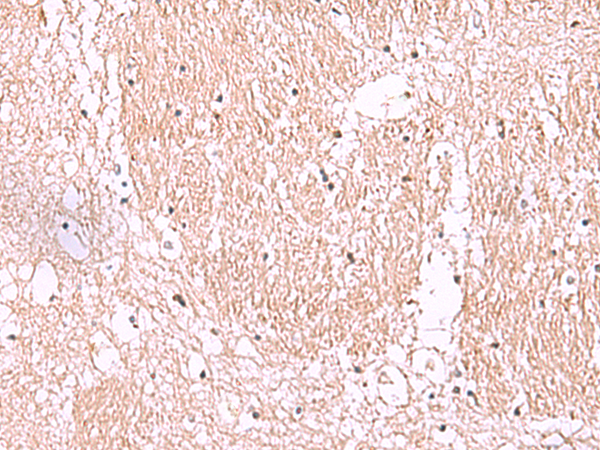

分类: 科研抗体货号: P10170别名: NML; KIAA0409应用: WB,IHC反应种属: Human, Mouse, Rat